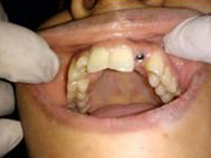

Single Tooth Implant

Drilled socket for Implant